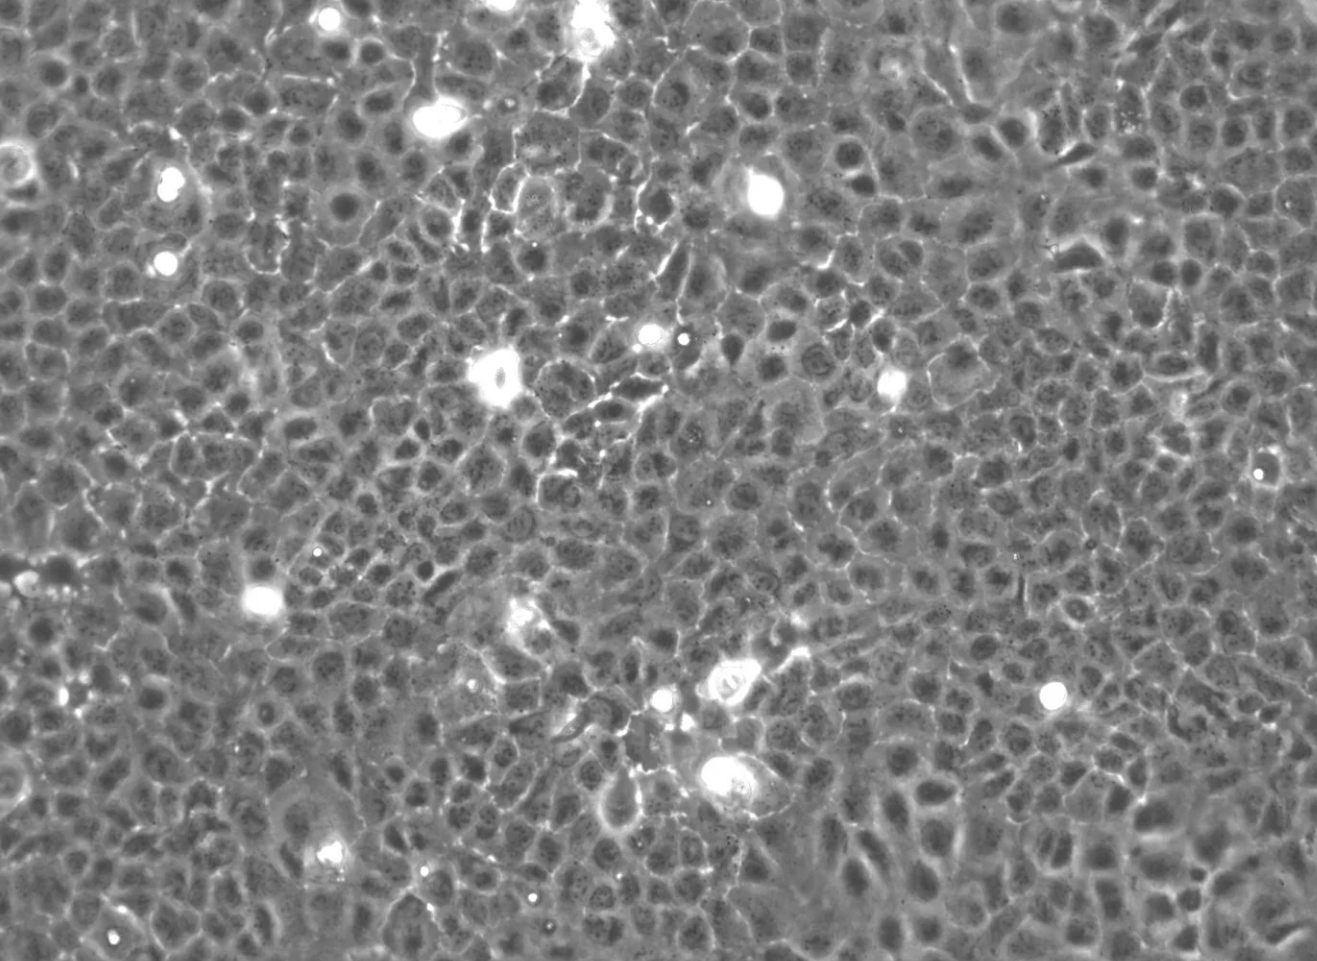

形態(tài)

上皮細(xì)胞樣

生長(zhǎng)特征

貼壁生長(zhǎng)